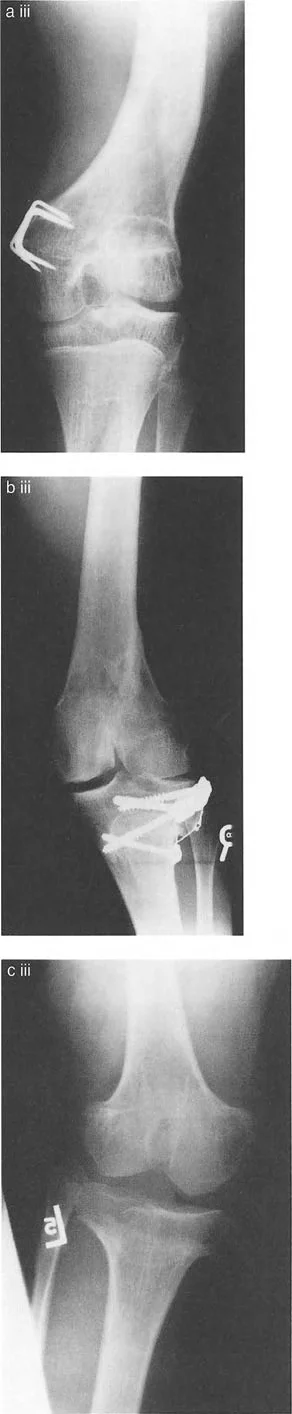

أمثلة كلاسيكية لتشوه خط مفصل الساق

- مرض بلونت (تقوس الساق): في مرض بلونت الشديد لدى الرضع أو المراهقين، تتميز الحالة بانخفاض شديد وميل إنسي للهضبة الظنبوبية الإنسية. إذا رسمت الخطين، فإن خطي الهضبة الإنسية والوحشية يكونان بزاوية حادة بالنسبة لبعضهما البعض، ويتقاطعان بالقرب من مركز الركبة. وهذا يخلق دفعاً تقوسياً شديداً أثناء المشي.

* التئام العظم بعد الصدمة بشكل خاطئ: كسر سالتر-هاريس لدى الأطفال أو كسر بين اللقمتين لدى البالغين يلتئم بشكل سيء ينتج عنه درجة مميزة و/أو سوء توجيه للقم.

* توقف النمو المركزي (تشوه ذيل السمكة): توقف النمو في المركز الدقيق لصفيحة النمو الفخذية البعيدة يتسبب في سوء توجيه اللقمتين وانحدارهما نحو المنتصف، مما يخلق مظهراً كلاسيكياً "لذيل السمكة" على صور الأشعة السينية الأمامية الخلفية.